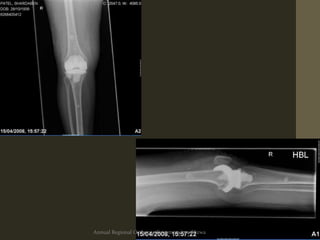

Patellar loosening

Diagnosis: Radiological

• Early Lysis/Lucencies

• Progressivelucent

lines

• Lytic area(s)

• Prosthesis position

• Stem movement

• Cortical perforation